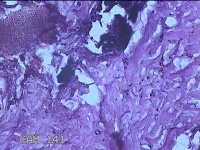

性别

女

年龄

27岁

临床诊断

乳腺脓肿

一般病史

发现右侧乳腺脓肿1个月余,伴局部疼痛不适。

标本名称

右侧乳头下方结节

大体所见

灰白暗红色结节0.8x0.5x0.3cm一个,表面糜烂。

组织没固定好